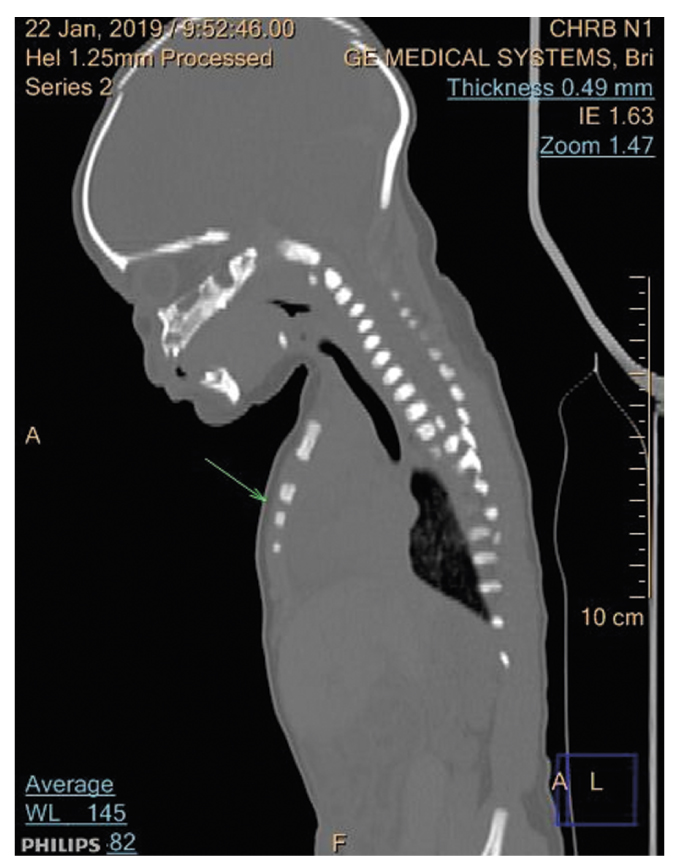

В декабре 2019 г. в помещении мусоросортировочного цеха Раменского района Московской области на сортировочной ленте обнаружен труп новорожденного ребенка мужского пола с фрагментом пуповины. Труп представлен двумя фрагментами: первая часть — головой, шеей, правой и левой верхней конечностью, грудной клеткой и верхней третью живота; вторая часть — тазом и нижними конечностями. Первая и вторая части трупа соединяются тканевой перемычкой (кожей с мягкими тканями) передней брюшной стенки (рис. 7).

Рис. 7. Труп ребенка, внешний вид: а — при обнаружении; b — КТ, 3D-изображение.

Fig. 7. Appearance of the corpse of the child: а — upon detection; b — 3D image.

При КТ основными находками были костные повреждения: множественные повреждения и переломы костей черепа (рис. 8, 9) — лобной кости, чешуи слева, глазничной и носовой части лобной кости слева, обеих теменных костей, затылочной кости (базилярной, латеральной частей и чешуи) со смещением, захождением и деформацией костных отломков, височных костей, тела и больших крыльев основной кости; расхождение швов мозгового и лицевого черепа с деформацией черепной коробки в виде уплощения с боков; перелом скулоорбитального комплекса справа; позвоночного столба (латеральное смещение С1-позвонка вправо, С7-позвонка влево); полная сепарация позвоночного столба с большим диастазом на уровне середины тела Th11-позвонка, с переломом тела позвонка; множественные переломы большинства ребер; полная сепарация всех ребер слева на уровне реберно-позвоночных сочленений, с диастазом; деформация грудинного конца ключицы справа; переломы крыла подвздошной кости справа, седалищной кости справа; неполный перелом средней трети диафиза правой бедренной кости, средней трети диафиза правой большеберцовой кости. Вещество головного мозга было в состоянии декомпозиции (см. рис. 8), представлено мягкотканным субстратом с наличием газа и плотных включений; воздухоносные пространства пирамид височных костей выполнены мягкотканным субстратом. Левое глазное яблоко деформировано, неправильной формы. Ушные раковины и наружный нос правильно сформированы, деформированы. Грудная клетка деформирована, гемитораксы асимметричны. Средостение представлено в виде отдельных мягкотканных элементов с наличием плотных включений. Сердце в размерах не увеличено, располагается вне грудной полости. Легочная ткань: легкие располагаются вне грудной полости, повышенной плотности (тотально уплотнены), не расправлены (рис. 10). В структуре легочной ткани прослеживаются элементы газа, отдельные — в виде трубчатых структур — вероятно, отображение бронхов. В толще легочной ткани и вокруг видны структуры высокой плотности — вероятно, инородные тела в сочетании с костными фрагментами. Визуализируются трахея и проксимальные отделы правого и левого главных бронхов; дистальнее просвет бронхов обрывается. Нарушение целостности брюшной стенки с полной эвентрацией органов. Полые и паренхиматозные органы представлены мягкотканными структурами без органной дифференциации, смешанными с инородными телами, чередующимися с множественными пузырьками газа. Газ определялся в мягких тканях, в том числе мошонке, грудной клетке, малом тазу, полости черепа, позвоночном канале.

Рис. 10. КТ: легкие располагаются вне грудной полости, тотально уплотнены, не расправлены.

Fig. 10. Computed tomography findings: the lungs are located outside the chest cavity, totally compacted, not straightened.

На основании полученных данных сделан вывод: новорожденный является зрелым, доношенным, продолжительностью внутриутробной жизни около 36 нед. Ребенок родился мертвым, о чем свидетельствуют данные предсекционного КТ (тотальное уплотнение обоих легких — нерасправленные легкие) и судебно-гистологического исследования. Повреждения при разделении туловища младенца образовались посмертно, скопления газа — в результате гнилостных изменений.